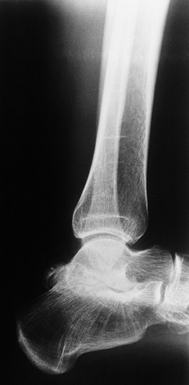

of involvement and is usually the first target joint in children after

they begin to walk. Progressive arthropathy is the rule. End-stage

ankle arthropathy is commonly manifested by severe joint surface

erosion, valgus alignment, and opposing exostoses on the tibia and

talus. Large synovial cysts occasionally invade the talus adjacent to

the ankle joint (Fig. 136.8). The subtalar joint is also subject to hemophilic arthropathy, although involvement is less common than in the ankle (Fig. 136.9).

![]() |

|

Figure 136.8.

Advanced arthropathy of the tibiotalar joint with surface irregularity, joint surface erosions, and abutting anterior exostoses. |